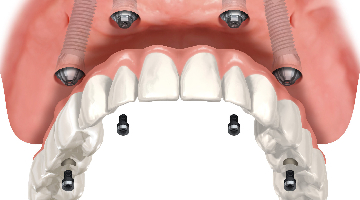

Chewing efficiency is greatly affected by how much of the teeth or bridgework in a given arch is fixed to the jawbone. Just as a person with a wooden leg would not walk as well as a person with a hinged and fitted carbon fiber prosthetic leg, a person with a tissue-supported denture will not chew as efficiently as a person with implant-supported bridges that are fused to the jawbone (figure 1).

A person chewing with upper and lower dentures will only achieve 20% (an average of 30% for the upper denture and 10% for the lower) of the chewing efficiency of a person chewing with a full set of natural teeth, whereas a person chewing with upper and lower implant-supported bridges will achieve 90% chewing efficiency (figure 2). (2)The ability to extract additional nutrients from the food bolus can have a significantly positive impact on a patient’s overall health. Studies have tied the use of implant-supported bridges versus dentures to an increase in life expectancy of seven years. (3) To maximize a patient’s health and reduce future costs, it is important to use a fixed prosthesis versus a removable one.